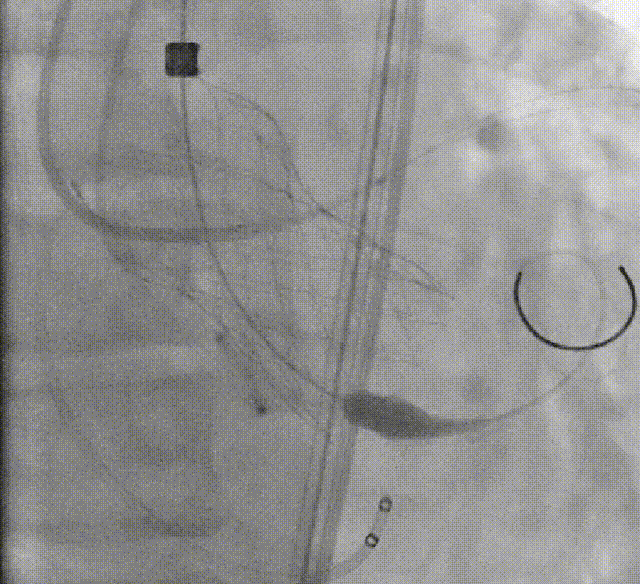

术者采用患者右侧主入路,顺利完成导丝和猪尾跨瓣等准备工作。进Landerquist超硬导丝,采用25mm球囊进行预扩,仔细评估冠脉风险后,决定对冠脉采取保护措施。根据球囊扩张情况,术中决定使用金仕生物的ProStyle预装干瓣TAV32。打开包装后,很迅速的完成了瓣膜和系统植入前的准备。输送过程系统和瓣膜轻松过弓并顺利跨瓣;开始初步释放,然后快速起搏下释放,发现位置略高后进行回收,重新定位后最终成功完成释放。反复造影发现冠脉存在阻塞风险,武汉协和团队按照风险预案在左冠植入4.0*18mm支架进行保护。术后显示左右冠脉血液灌注通畅,术后超声测量峰值流速1.45m/s,峰值压差8mmHg,几乎无瓣周漏。入路闭合顺利,无心脏及血管并发症,手术成功。

球囊扩张

初步释放

再回收后释放,术中冠脉评估

系统撤出

支架植入